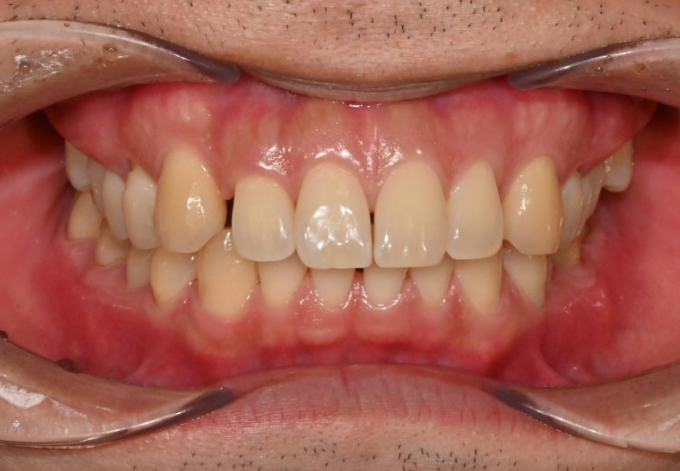

앞에서 보면 윗니가 아랫니를 많이 덮어서 앞니가 깊게 물리는 과개교합, 중심선 불일치,벌어진 앞니 등이 보입니다.

경미한 총생과 중심선 불일치, 가위교합, 벌어짐, 과개교합 문제가 있는 상황입니다.

인비절라인 라이트로 충분해서 인비절라인 라이트 권유드렸습니다.